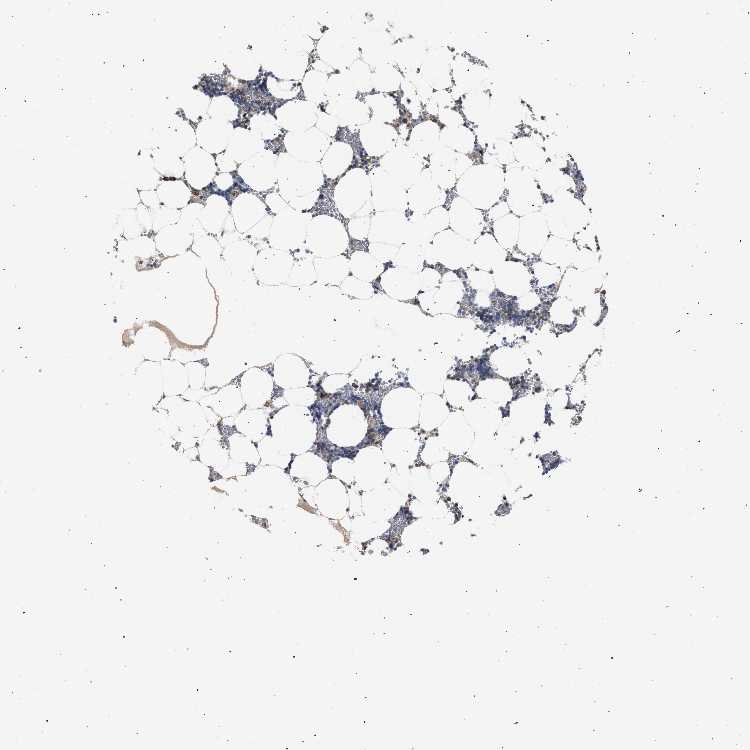

BONE MARROW - Antibody stainingi

Antibody staining in the annotated cell types in the current human tissue is reported as not detected, low, medium, or high, based on conventional immunohistochemistry profiling in selected tissues. This score is based on the combination of the staining intensity and fraction of stained cells.

Each image is clickable and will lead to virtual microscopy that enables deeper exploration of all samples and also displays staining intensity scores, fraction scores and subcellular localization as well as patient and tissue information for each sample.

Antibody HPA022015

Hematopoietic cells Medium